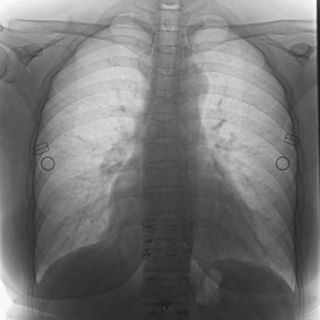

不同于常規(guī)DR只能進(jìn)行平片攝影檢查,普利德多功能動(dòng)態(tài)平板DRF動(dòng)靜兼?zhèn)?,可?shí)現(xiàn)大幅面低劑量透視檢查,在日常的體檢工作中,比如胸部及肺部檢查,可對(duì)重疊部位病變進(jìn)行可視化觀察及多角度旋轉(zhuǎn)體位,發(fā)現(xiàn)疑似病灶可瞬時(shí)完成高清點(diǎn)片,顯著提高診斷的準(zhǔn)確性。

動(dòng)態(tài)采集幀率最高可達(dá)30/s,影像細(xì)膩流暢,便于醫(yī)生對(duì)細(xì)微病變觀察。17×17英寸大幅面成像,在透視過程中能對(duì)患者的胸部腹部等部位實(shí)現(xiàn)大范圍覆蓋,便于從整體上觀察組織信息,更加全面且精準(zhǔn)的捕捉病灶。